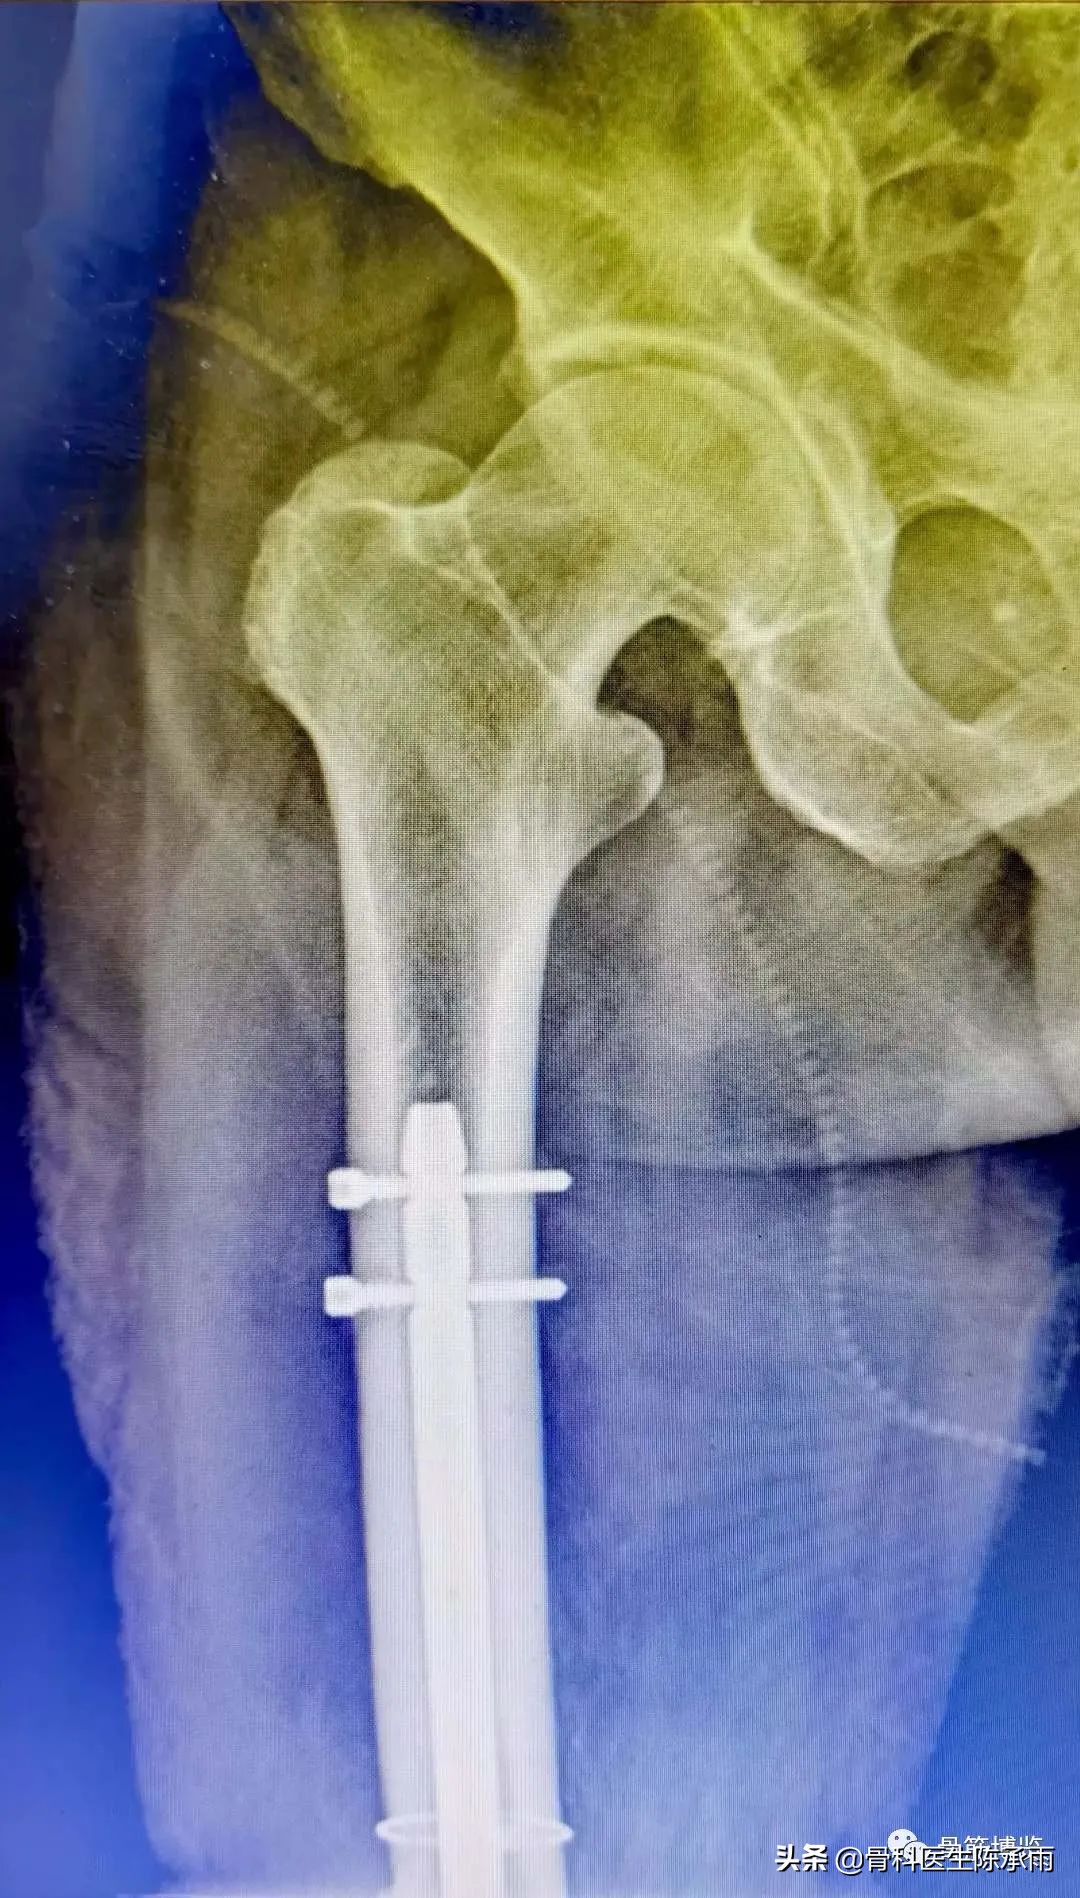

这2例患者皮肤条件差,全身多发骨折,小腿皮肤条件差,1例筋膜高压切开,1例整个小腿布满张力性水泡,胫骨骨折都在伤后30天才能手术。